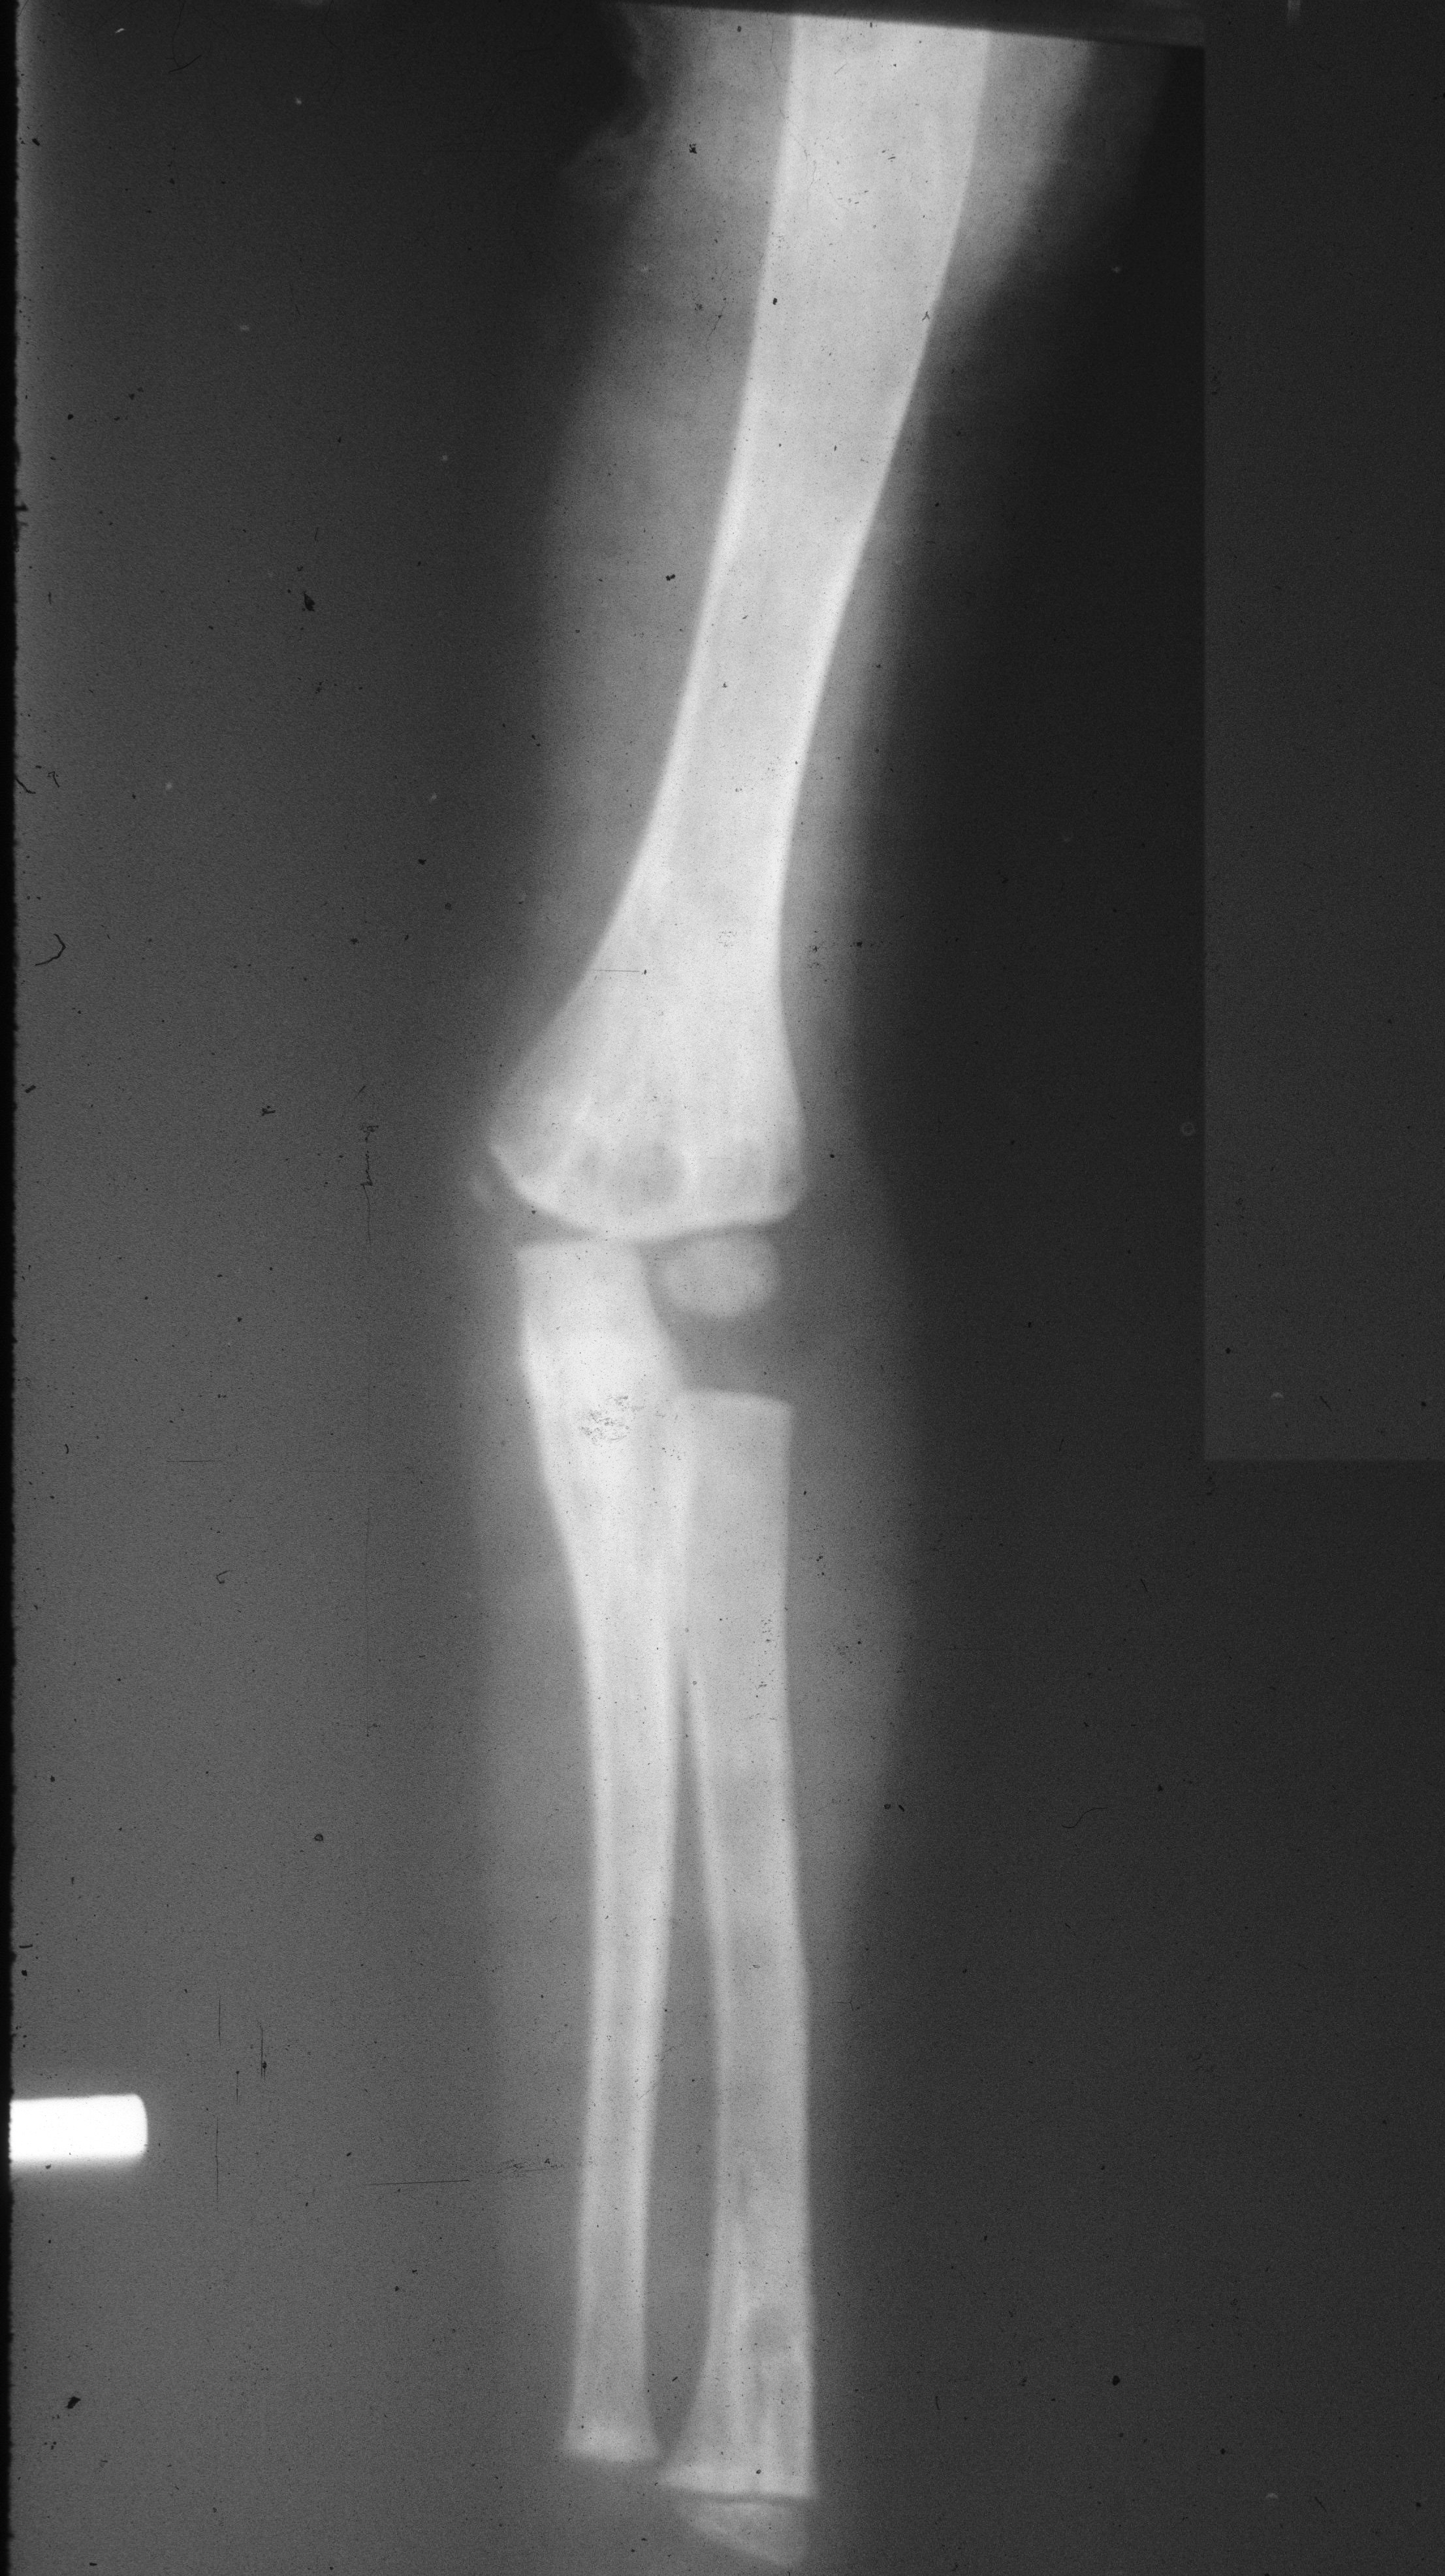

In the radius and ulna, cystic lesions may be noted or diffuse sclerosis with deformity (Figure 14a,b,c,d).

Figure 14: FD – (a, b) Radius, (c, d) Ulna In the hands, monostotic is rare.